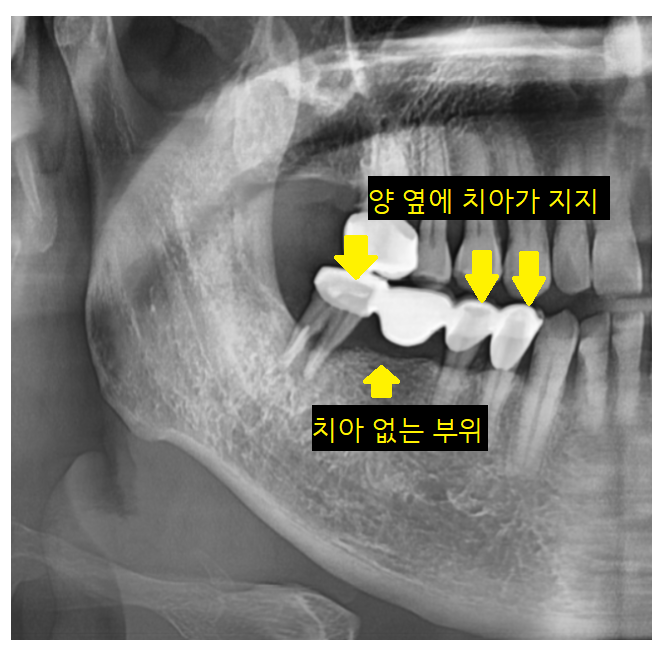

bridge = 다리라는 뜻이죠~

임플란트 개발 전에는 치아가 빠졌을 때

브릿지 치료로 상실된 치아 부분을 대체하였습니다.

양옆에 치아에 걸어서

치아가 빠진 부분을 채워주는 거죠~

단점은 양옆의 내 치아

생니를 깎아서 씌워야 했는데요.

4개가 연결되어 있지만

검사 후 잇몸뼈가 남아있는 부분은

그대로 쓰시기로 했습니다.

연결된 오래된 브릿지 보철을 잘라서

뽑을 건 뽑고

살릴 수 있는 것은 살려서 진행